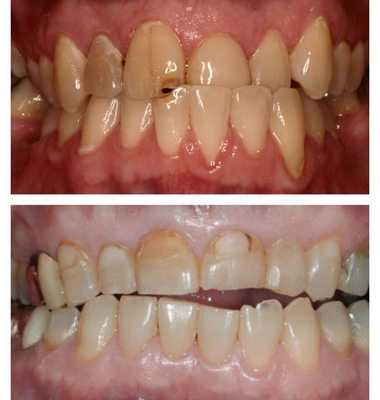

Нередкий признак прогрессирующей патологии с осложнениями — это некариозные поражения твёрдых тканей зубов: клиновидные дефекты, сколы эмали, патологическая стираемость зубов, недолговечность ортопедических конструкций или пломб.

Осложнения со стороны твёрдых тканей зубов и пародонта

Эмаль — самая прочная ткань в организме, но под влиянием постоянно повышенной нагрузки на ней появляются микротрещины, которые затем приводят к сколам, появлению клиновидных дефектов и повышенной чувствительности зубов.

Периодонтальные связки, окружающие зуб, также имеют свой функциональный запас. При чрезмерной нагрузке, особенно на отдельные группы зубов, в этих связках развивается защитная реакция. Она может проявляется воспалением и дальнейшим разрушением структур.

Клинический осмотр лица помогает выявить выраженную асимметрию и пропорциональные несоответствия. При осмотре полости рта определяют тип перекрёстного прикуса. Оценивается состояние твёрдых тканей зубов: обнаруженные клиновидные дефекты, патологическая стираемость, сколы эмали, а также короткий срок службы пломб может косвенно свидетельствовать о наличии окклюзионных перегрузок, тем самым подтверждая поставленный диагноз. Слизистая губ и щёк нередко имеет отпечатки зубов из-за накусывания слизистой в месте перекрёстного положения зубов.